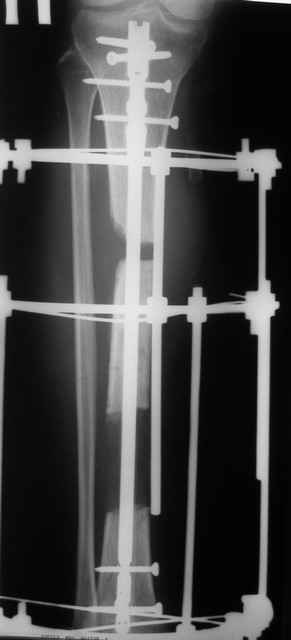

Кратко: мужчина за 60 лет получил травму 28 лет назад (переехало автобусом). Оперировался десятки раз, в итоге с очередным патологическим переломом, хронической язвой и гипсовой лонгетой попал ко мне... Объективно - остеомиелит, инфицированный ложный сустав (или как его назвать), флегмона по наружной поверхности

голени, укорочение около 5 см.

На операции резекция 8 см, внешний остеосинтез,одновременное сближение примерно на 4 см, а затем постепенное сближение до полного контакта в течение 3 недель. Рана с патологически измененными краями, имевшая на операции размеры примерно 4-5 на 10-12 см закрылась самостоятельно в течение примерно 2-х мес. Ну не самостоятельно, конечно, а с нашей помощью, но без пластики.

Сейчас в аппарате вытянул около 6 см в верхней трети.